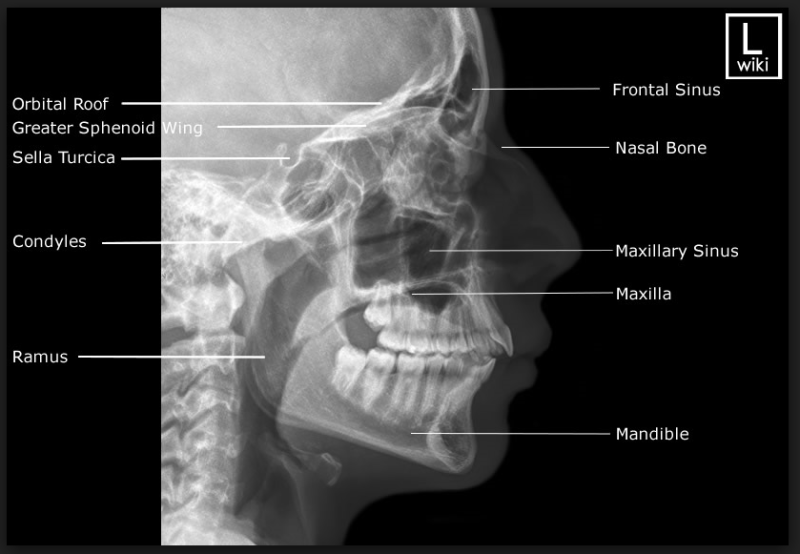

Landmarks of Cephalometric Xray. Abbreviations of fig. 2 PNS What Is Pns X Ray All are normally paired, except. The nasal cavity is a system of air channels that connect the nose with the back of the throat. Patient position, technical parameters, and criteria for success for lateral and pa views. Paranasal sinuses enable the circulation of the air breathed in and out of the respiratory system(2). The paranasal sinuses are derived from ectoderm. What Is Pns X Ray.